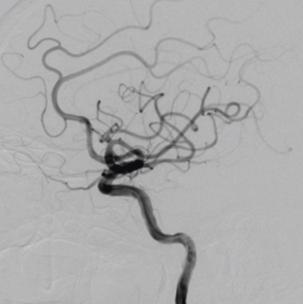

再行造影见动脉瘤不显影,无造影剂渗漏,血管重建满意。

3D重建图示支架贴壁良好。